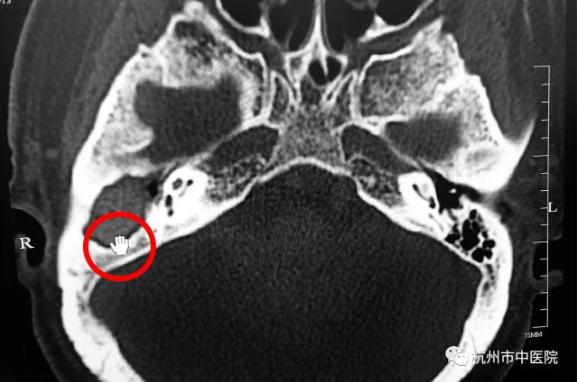

为明确诊断,梅医生又为徐大伯开出了螺旋CT检查,结果显示大伯的右侧外耳道骨壁、乳突区及听小骨骨质均被破坏、吸收,这些症状可能就是胆脂瘤破坏听小骨的传导功能而引发听力下降,又侵犯到面神经引起的面瘫的结果,如果再不及时进行干预,侵犯入脑就会引发生命危险。